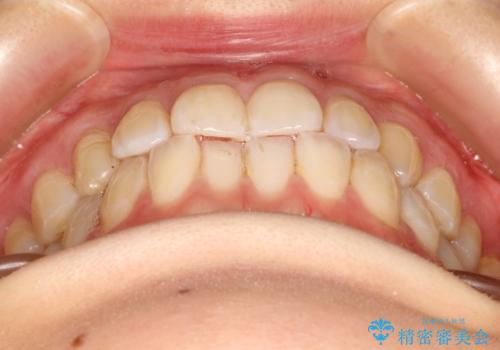

- 前歯の歯並びの改善を希望され来院された患者様です。

一度矯正治療をしたが、リテーナーをさぼってしまったため後戻りをしてしまった症例です。

初診時の歯並びの状態としては、上下ともに前歯部に限局した軽度ののがたつき(叢生)がある状態でした。